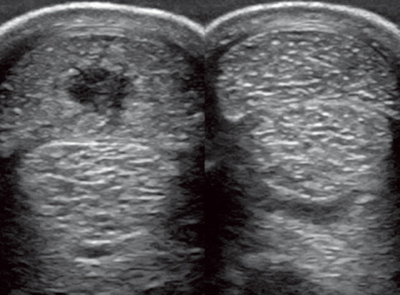

上圖為受傷肌腱的B超顯示,圖右為正常對(duì)比。可見圖左位于最上方的指淺屈肌腱體積變大(腫脹),中間出現(xiàn)深色區(qū)域(損傷)。B超檢查在治療筋腱軟組織損傷中尤為重要,在整個(gè)治療過程中,B超可以探查出病變部位的受損情況和恢復(fù)狀況,獸醫(yī)會(huì)根據(jù)B超探查的結(jié)果,制定下一步的治療和恢復(fù)計(jì)劃。